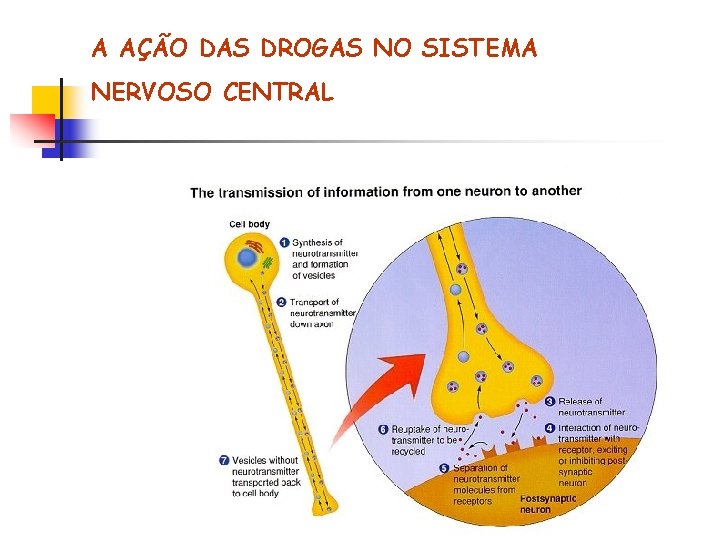

A AÇÃO DAS DROGAS NO SISTEMA NERVOSO CENTRAL O NEURÔNIO Axônio (pré-sinapse) Dendritos (pós-sinapse)

A AÇÃO DAS DROGAS NO SISTEMA NERVOSO CENTRAL A COMUNICAÇÃO ENTRE OS NEURÔNIOS

A AÇÃO DAS DROGAS NO SISTEMA NERVOSO CENTRAL A SINAPSE

A AÇÃO DAS DROGAS NO SISTEMA NERVOSO CENTRAL